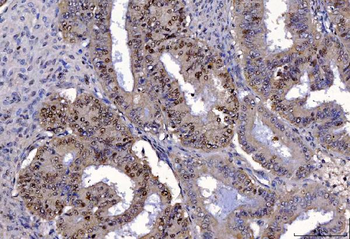

FEN1 Antibody

Catalog Number: orb193665

| Description | FEN1 Antibody |

| Clonality | Polyclonal |

| Species/Host | Rabbit |

| Conjugation | Unconjugated |

| Reactivity | Human, Mouse, Rat |

| Tested applications | IF, IHC, WB |

| Antibody Type | Primary Antibody |